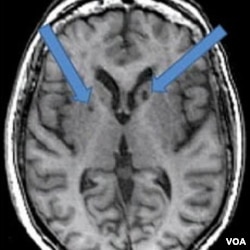

Hasil MRI atas otak pasien yang pernah terkena stroke dua kali. Panah menunjukkan adanya bintik-bintik gelap yang dulunya adalah sel-sel sehat yang mati akibat gumpalan darah yang masuk ke otak.

Pada hasil pemindaian pasien stroke, tampak lubang gelap berisi cairan. Psikolog syaraf Adam Brickman pada Fakultas Kedokteran Universitas Columbia, mengatakan ada bintik-bintik gelap yang dulunya adalah sel-sel sehat yang mati akibat gumpalan darah yang masuk ke otak.